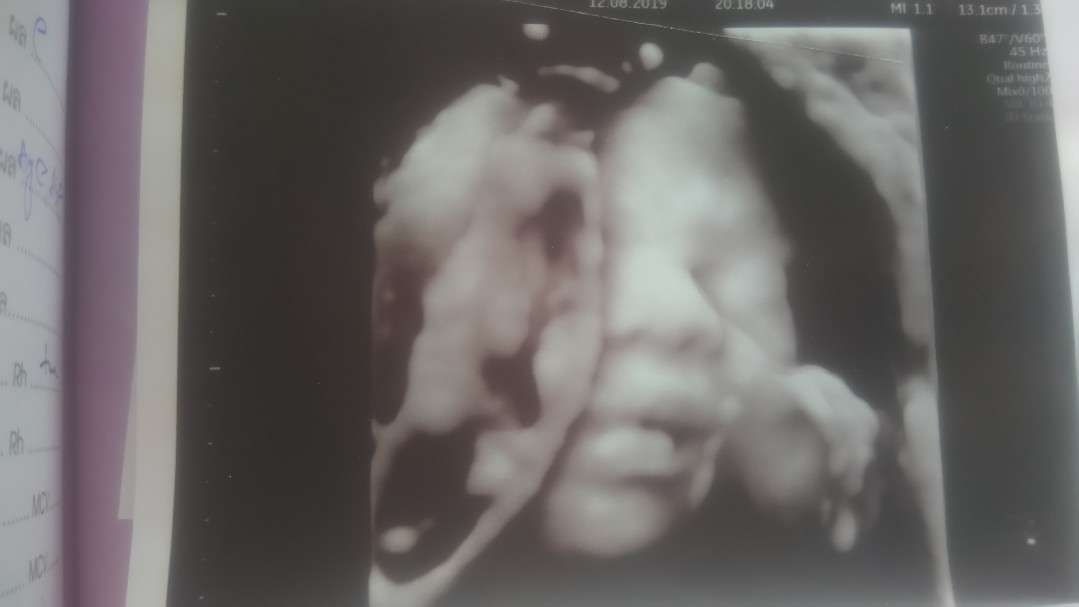

5เดือน

เเม่ท่านไหน5เดือนเห็นเเบบนี้ไหมค่ะ โชว์กันหน่อยค่ะเเม่ๆ

ตอน 5 เดือนค่า 😁

25w ผญ จ้า 3D